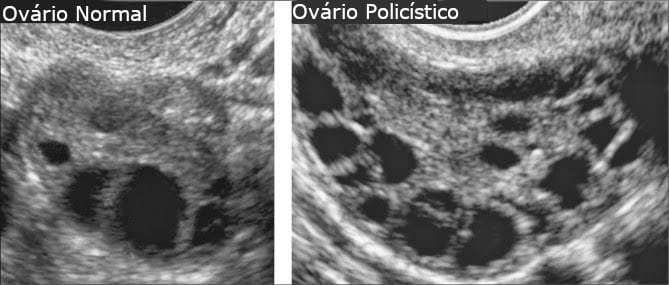

USG na SOP:

Pelo menos 12 folículos medindo entre 2 e 9mm ou volume ovariano maior que 10 cm3 .

Critérios de Rotterdam para SOP:

ovários policísticos ao USG(25% das mulheres normais podem ter)